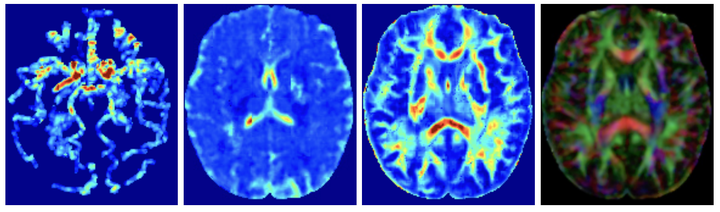

This software uses a learning framework (YETI) building on an auto-encoder structure between 2D and 3D image time-series, which incorporates an advection-diffusion model to capture blood perfusion. To help with identifiability, the deep learning model is trained via simulated data from an advection-diffusion simulator. Instead of directly learning the velocity and diffusion tensor fields of the advection diffusion equation, we use representations that assure incompressible flow and symmetric positive semidefinite diffusion fields.